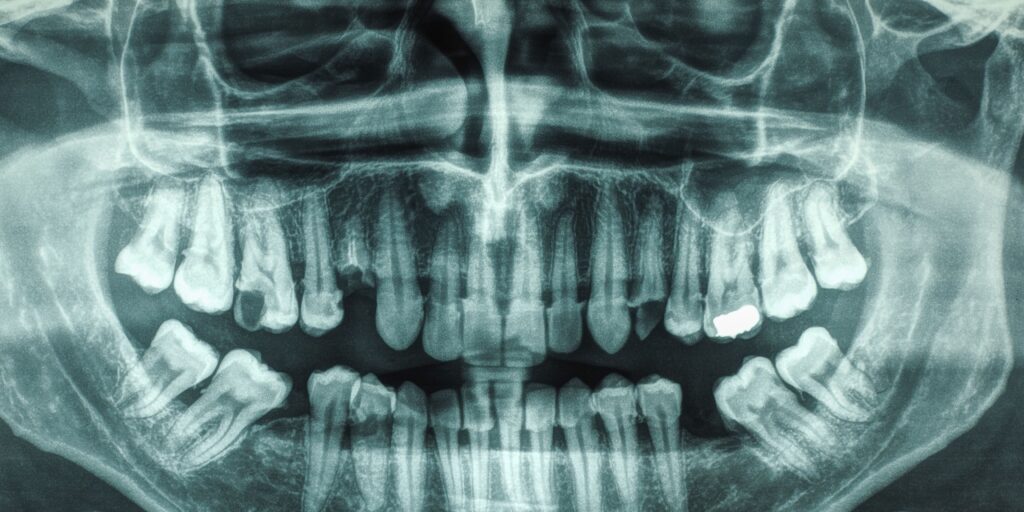

Why Some People Have 32 Teeth And Some Have Just 28 Teeth Chat With

Indian Woman 26 Crowned Guinness World Record Title For Having Most